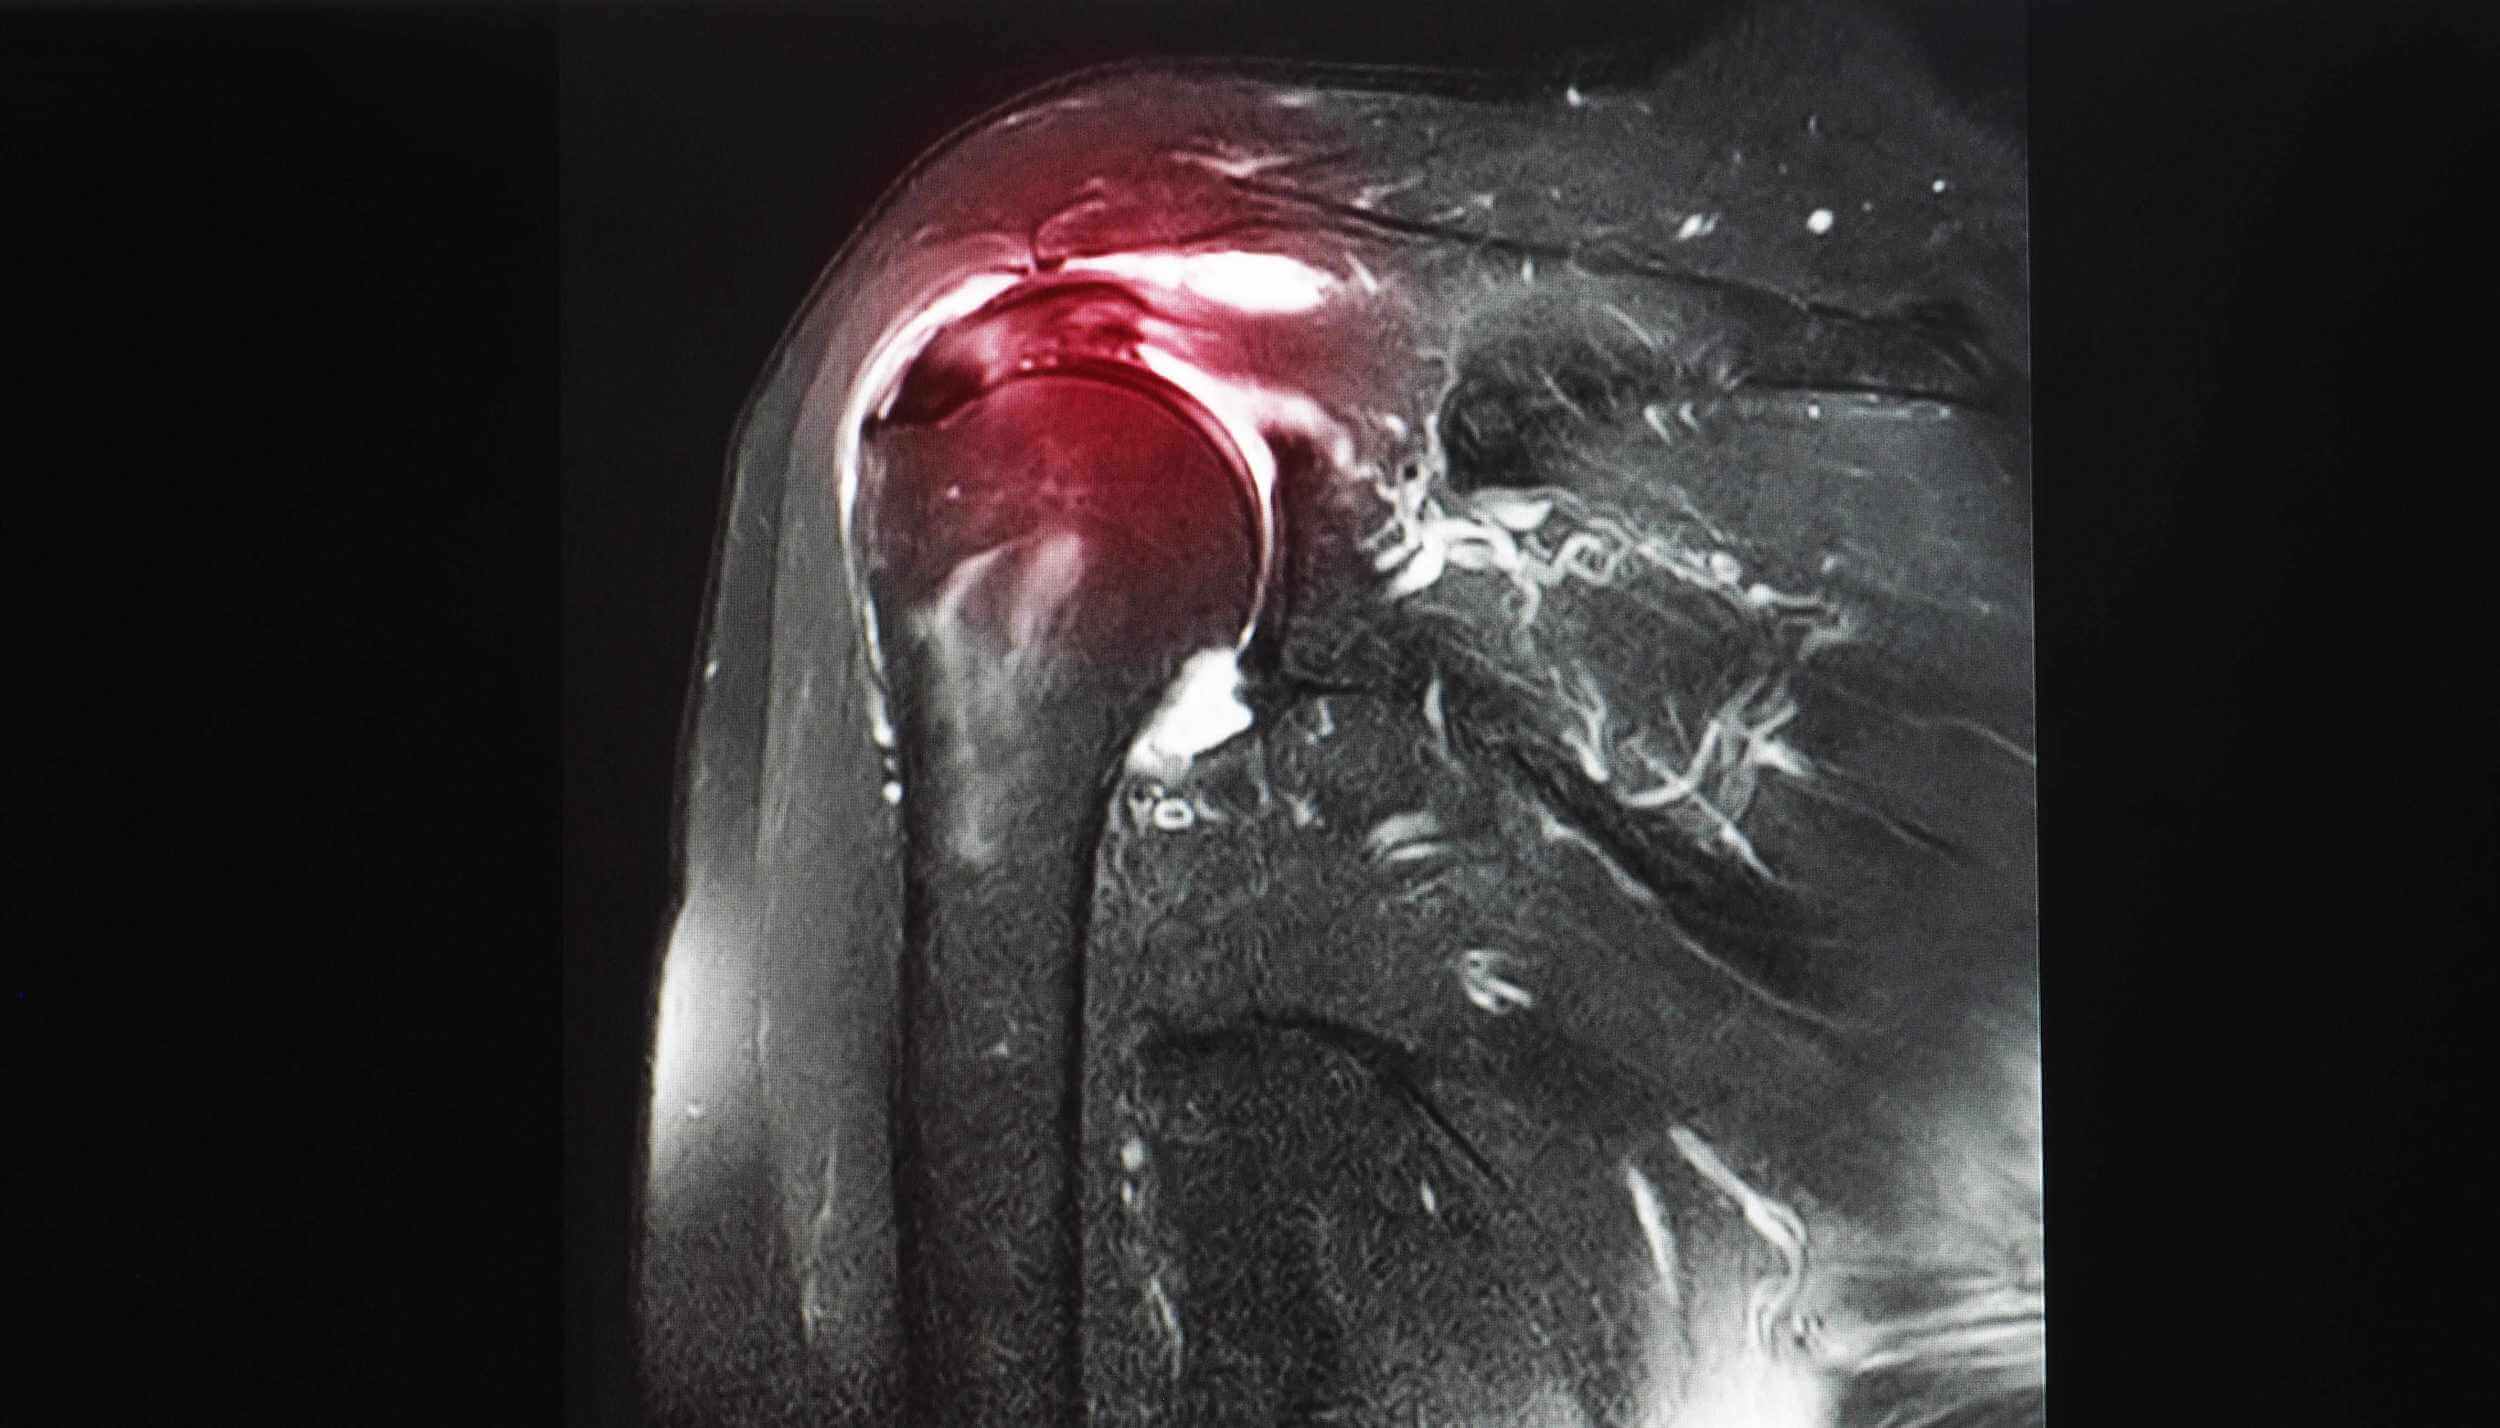

Zanesljiva diagnostična metoda za pregled rame, kjer obstaja sum na kalcinacije je ultrazvočna preiskava (UZ) pri specialistu radiologu. Z ultrazvočnim slikanjem se natančo določi lokacijo kalcijevih kristalov in njihovo velikost, lahko pa se uporablja tudi kot metoda spremljanja napredka konzervativnega zdravljenja kalcinacije rame.